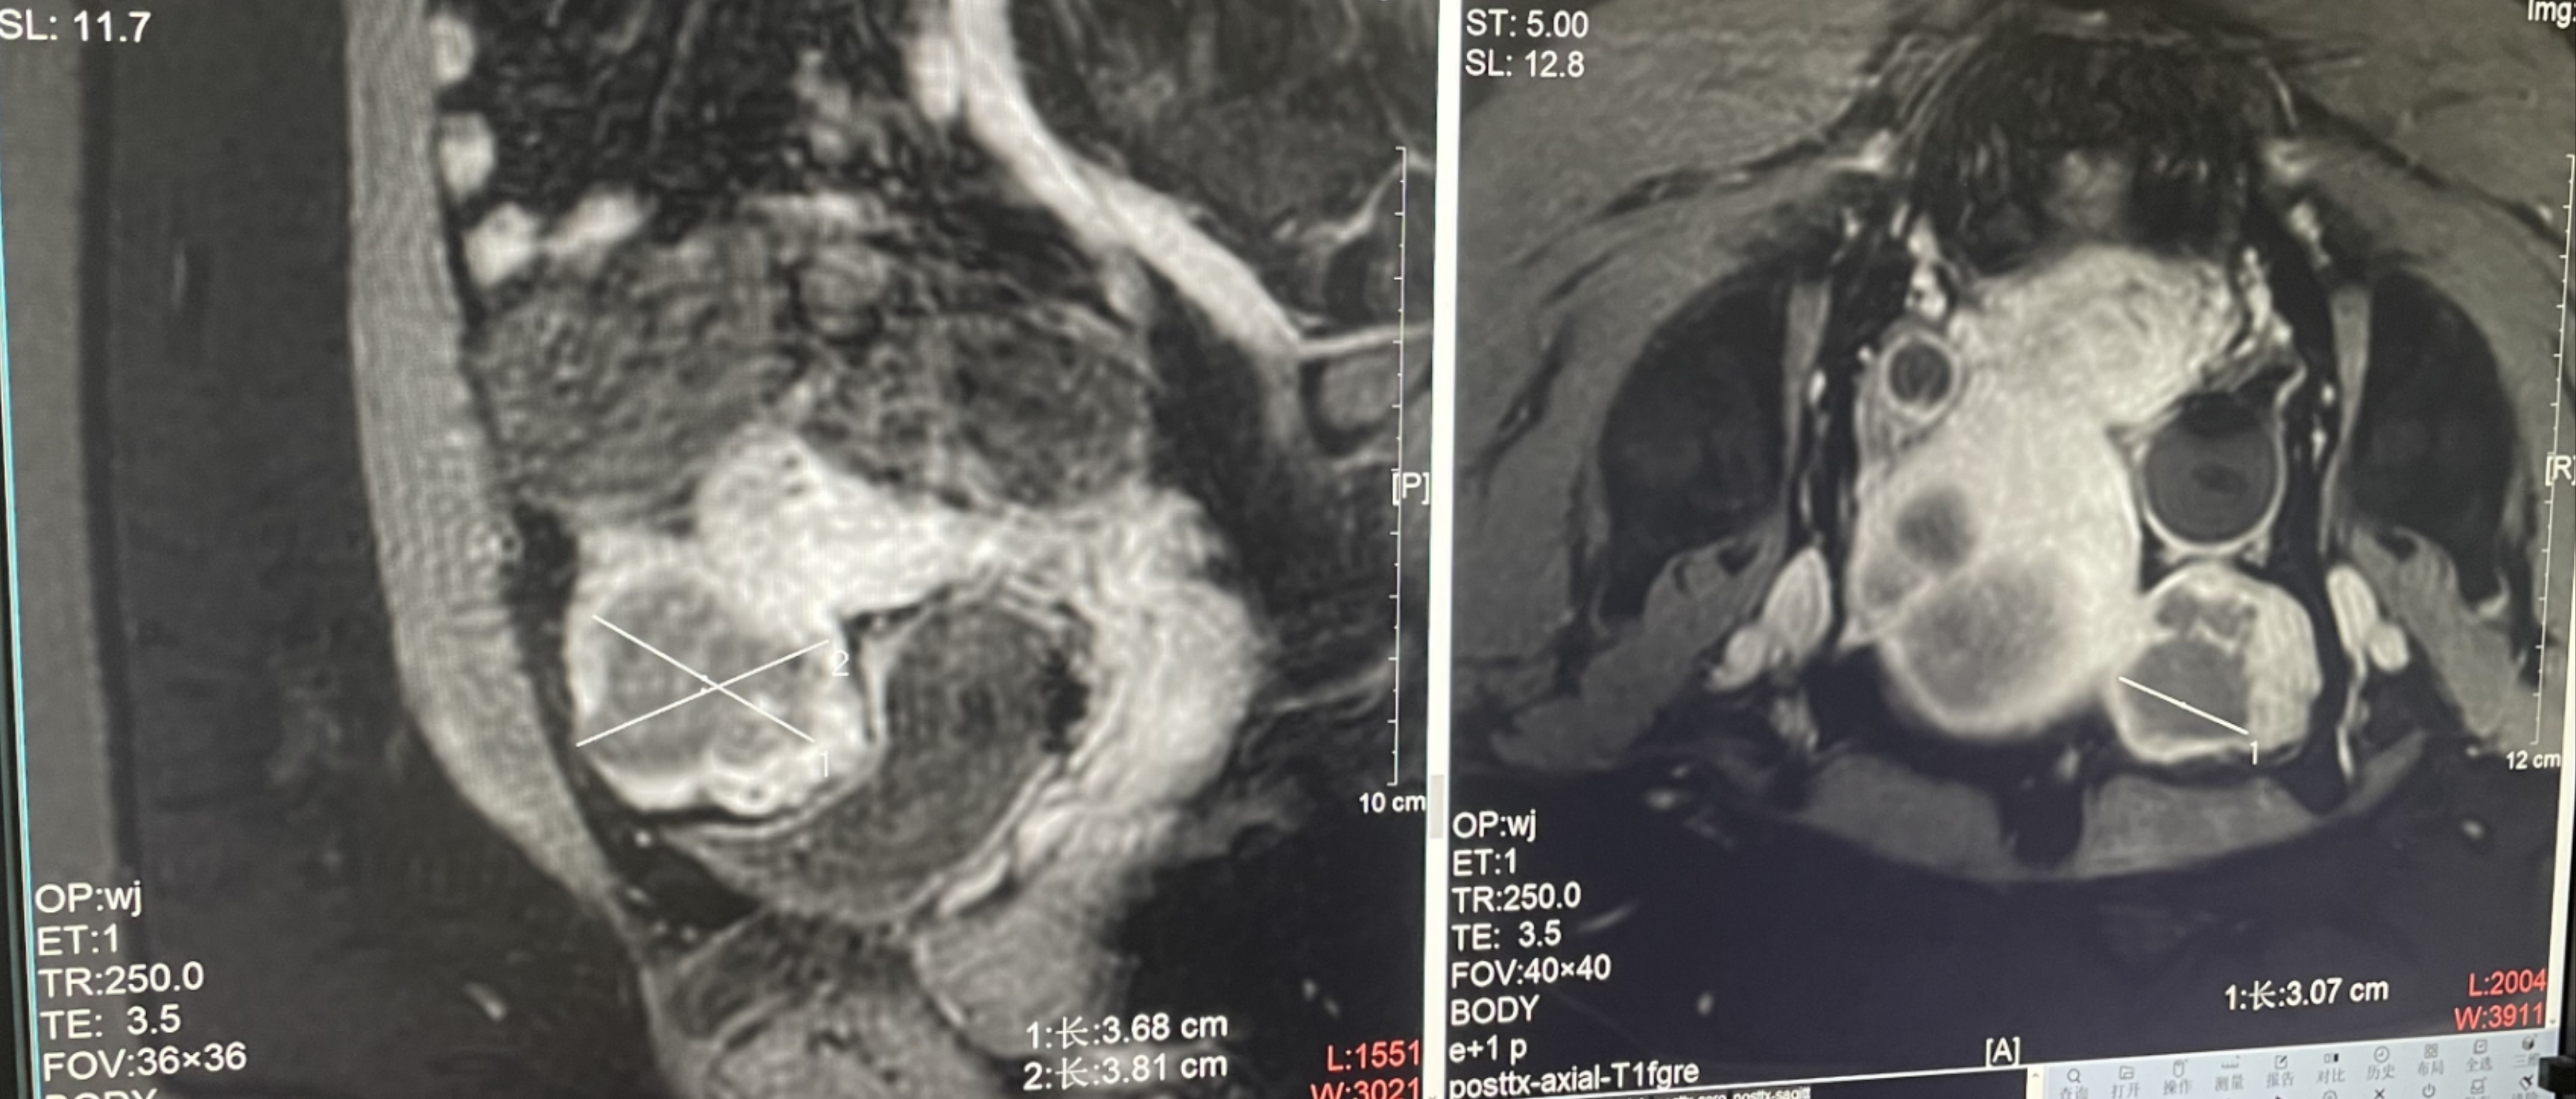

進一步了解收起

子宮腺肌癥

患者信息:女,38

診斷:子宮腺肌癥

病灶尺寸:約為40*37*40mm

ROT深度:病灶的ROT中心距離皮膚45mm

術后評估:術后造影增強圖像顯示消融區(qū)域(右側)與病灶區(qū)域(左側)重合度較好,非灌注區(qū)域連續(xù)且一致。

結論:對該病灶具有非常好的消融效果,治療過程中,溫度上升曲線符合預期,每個被治療的靶點240CEM區(qū)域體積較大、外形飽滿、連續(xù)。病灶消融良好,NPV體積比約80.6%。